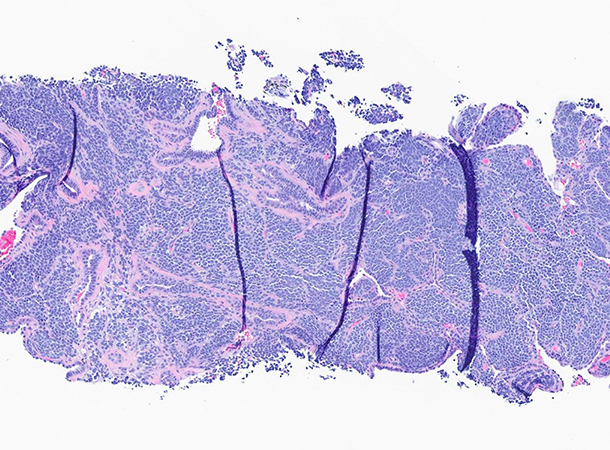

A 74-year-old woman, never smoker, with no significant past medical history, was found to have an incidental left upper lobe lung nodule following a fall. The lesion showed progressive growth, and a biopsy was performed (see Figures 1 through 6).